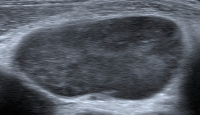

Abbildung 5: Äußere Form des Lymphknotens. Die Außenkontur des Lymphknotens ist kugelig. B-Zell-Lymphom.